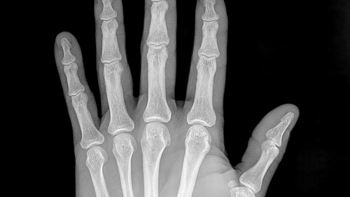

El Complejo Asistencial Universitario de Salamanca ha potenciado su Servicio de Radiodiagnóstico con la puesta en marcha de una unidad de radiología infantil, que ha iniciado su actividad a mediados del presente mes de noviembre con la apertura de las agendas de trabajo referidas a radiología convencional y ecografía específica para pacientes pediátricos.

La creación de esta unidad pretende dar una mayor calidad asistencial para los menores de 14 años, ya que sus patologías y tratamientos presentan importantes diferencias respecto a los adultos. Además, estos pacientes han de ser atendidos con protocolos radiológicos distintos que potencien la radio-protección en este grupo de edad puesto que los niños son más sensibles a la radiación que los adultos.

Esta unidad radiológica específica ha implicado en su creación a distintos servicios y niveles del Hospital Clínico Universitario y ha supuesto la adopción de protocolos específicos para menores de 14 años en las exploraciones radiológicas convencionales y de tomografía axial computerizada.

Asimismo se ha dotado al Servicio de Radiodiagnóstico con un nuevo ecógrafo de alta gama de múltiples sondas pediátricas y con programas específicos para estas edades y se han adquirido los medios de protección radiológica junto a las sujeciones oportunas para pacientes pediátricos, al objeto de disponer de todo lo necesario para realizar este tipo de exploraciones con la mayor calidad y la menor radiación posible.